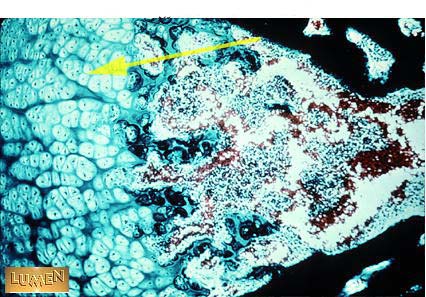

Hypertrophied Cartilage